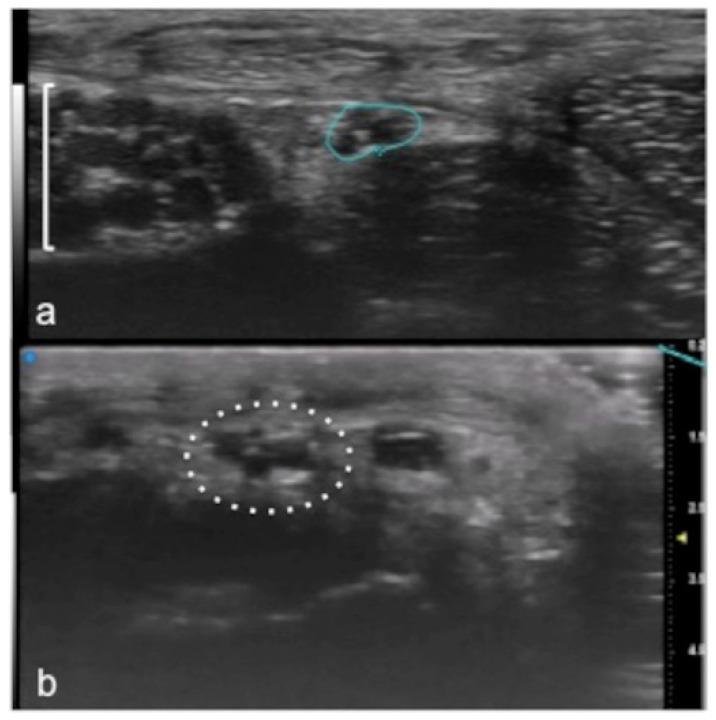

Musculoskeletal ultrasound involves the study of many superficial targets, especially in the hands, wrists, and feet. Many of these areas are within the first 3 cm of the skin surface and are ideal targets for ultra-high-frequency ultrasound. The high spatial resolution and the superb image quality achievable allow foreseeing a wider use of this novel technique, which has the potential to bring innovation to diagnostic imaging.

肌肉骨骼超声涉及对许多浅表目标的研究,尤其是在手部、腕部和足部。这些区域中的许多都位于皮肤表面的前3厘米内,是超高频率超声的理想目标。可实现的高空间分辨率和卓越的图像质量使得有望更广泛地使用这种新技术,它有可能给诊断成像带来创新。